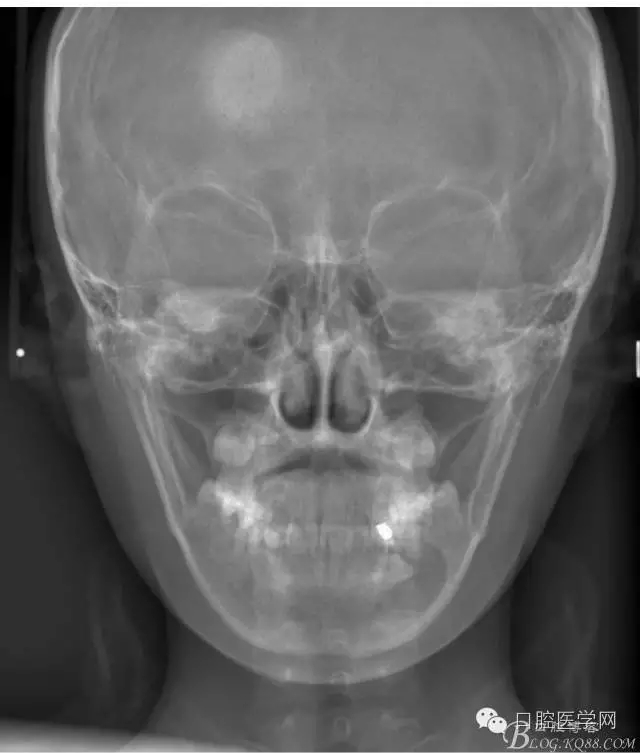

下頜囊腫伴上下頜正畸治療

患者,女,13歲。要求矯治排齊上下前牙。

查:右側(cè)第二前磨牙第一乳磨牙恒尖牙頰側(cè)前庭溝隆起,捫有乒乓球感。曲斷及CT示:右側(cè)第二前磨牙第一乳磨牙恒尖牙根尖區(qū)有一囊腫,頰舌側(cè)骨板極薄,牙根無(wú)吸收,第二前磨牙牙根位于囊腫中,第一雙尖牙牙冠遠(yuǎn)中水平向阻生,牙冠位于囊腫中。經(jīng)協(xié)議:手術(shù)摘除創(chuàng)傷大,同意開(kāi)創(chuàng)引流保守治療。